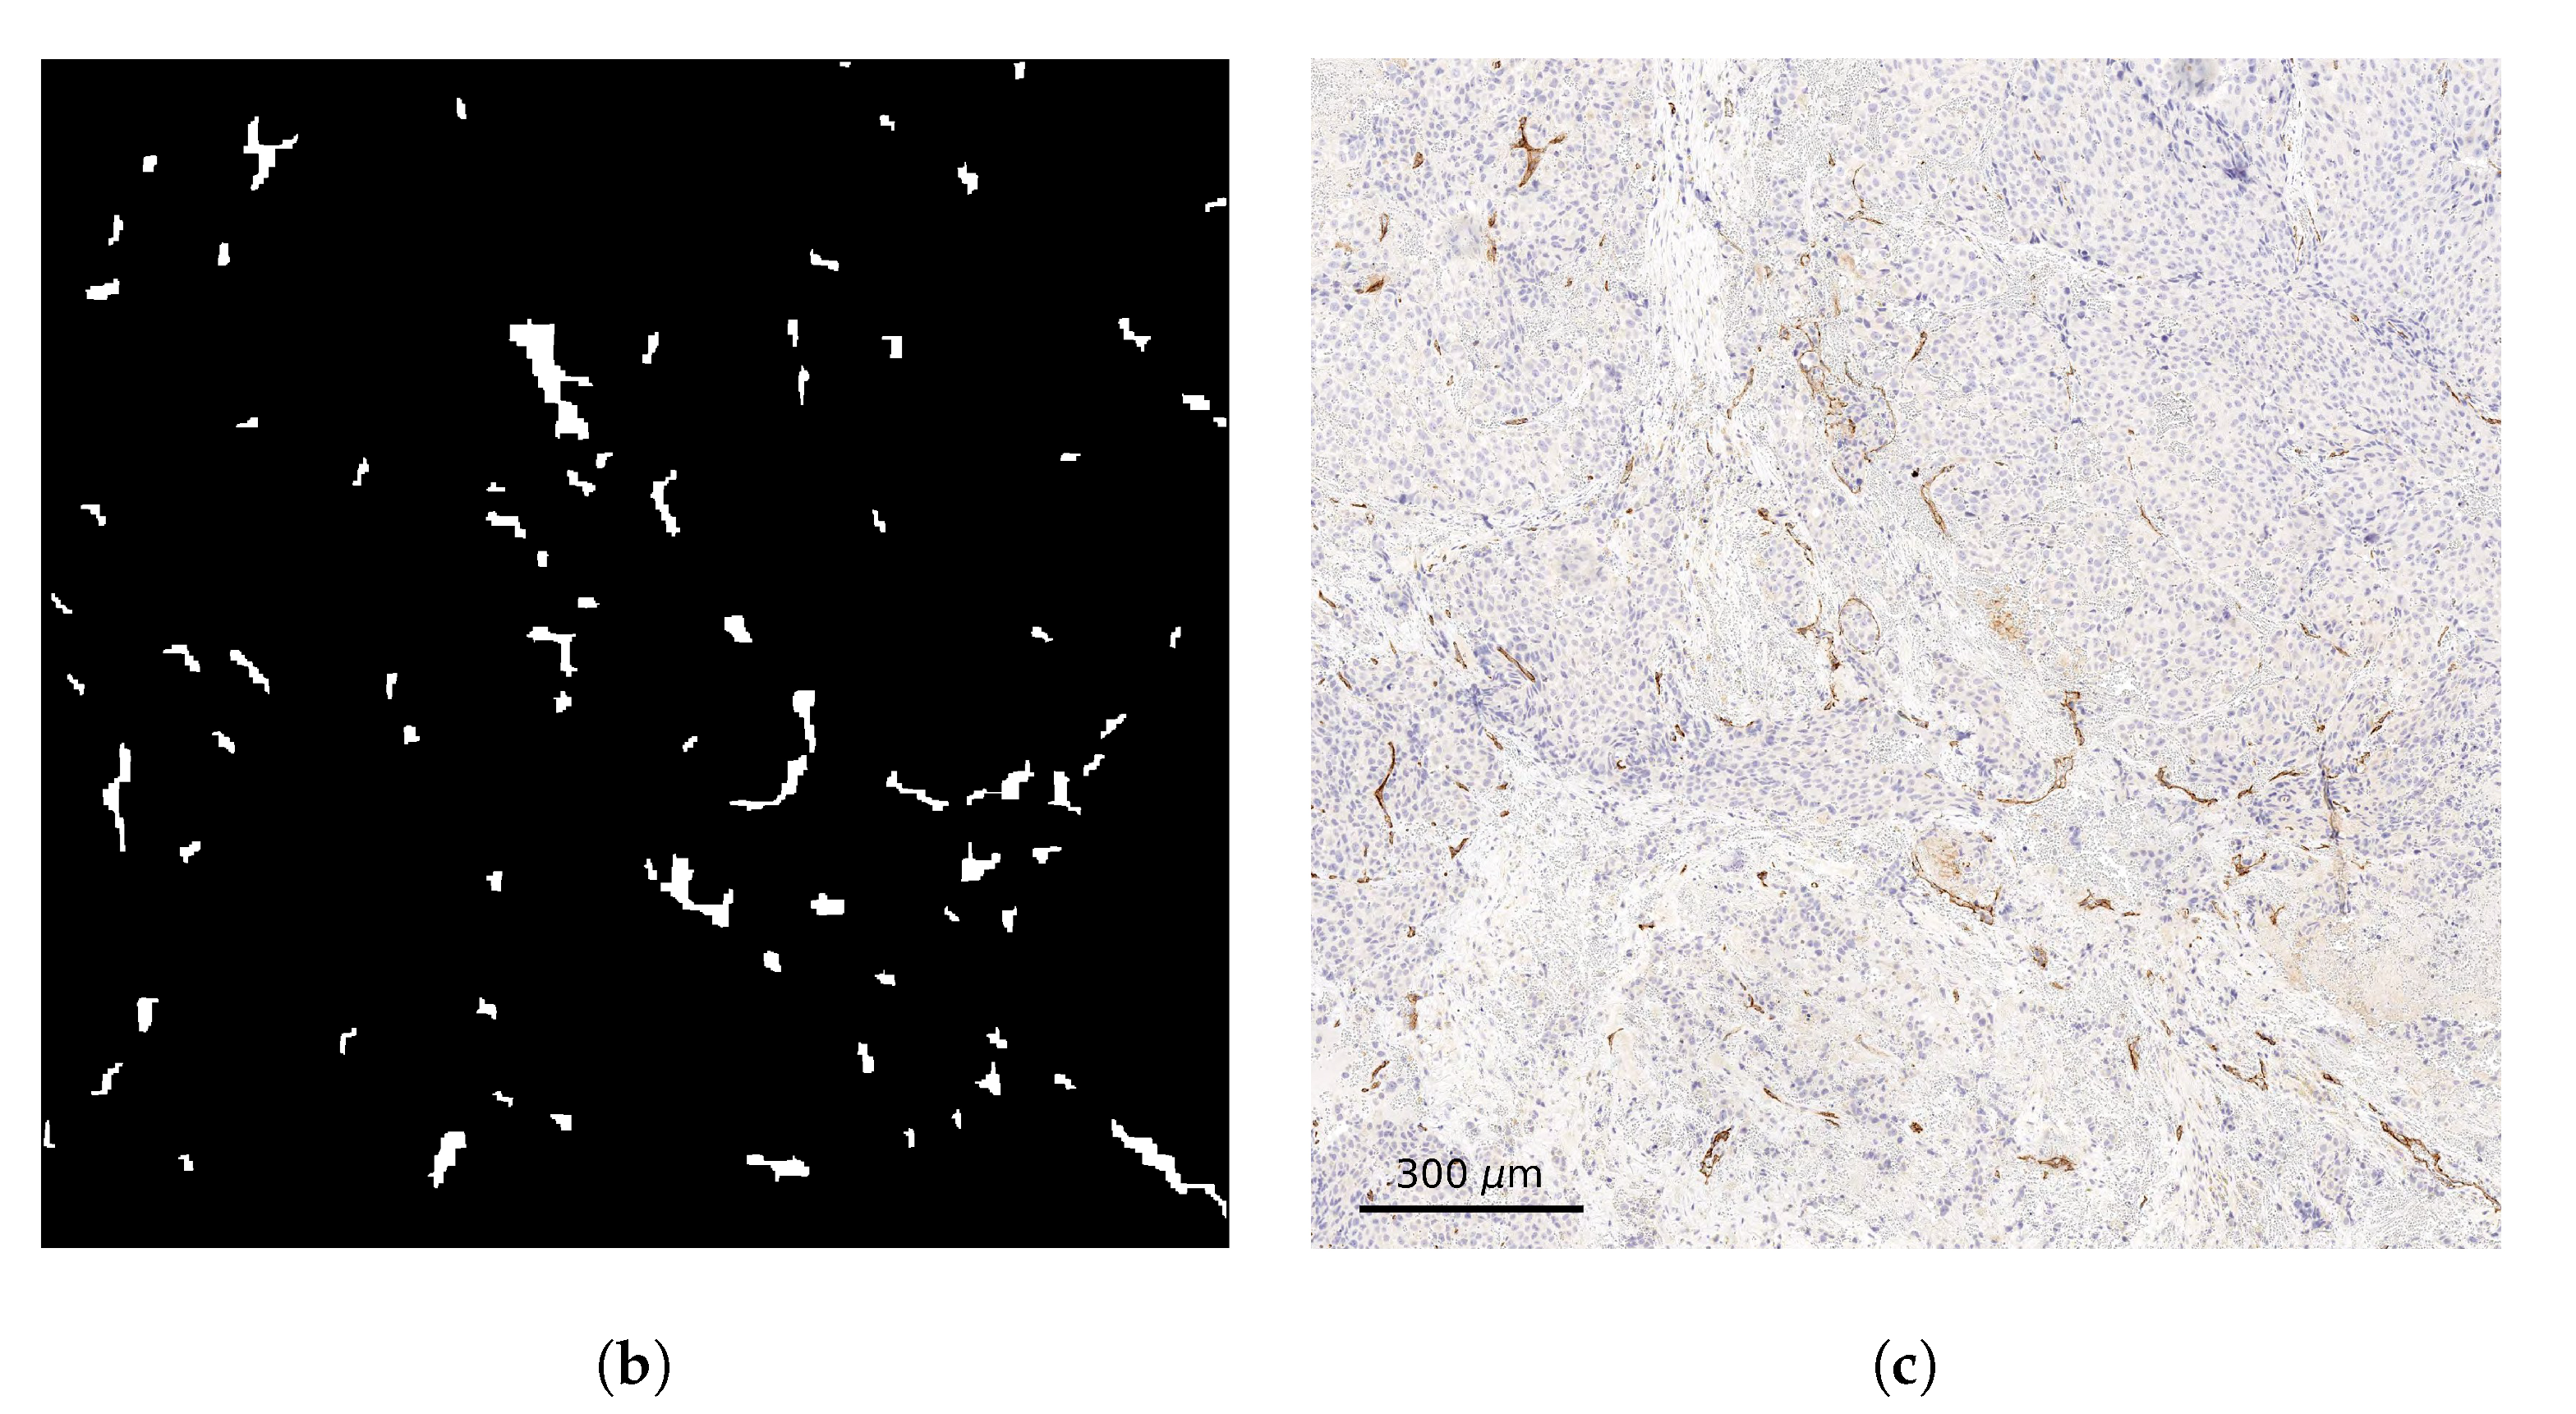

3.1. Tissue Oxygenation and Oxygen Dependent Tissue Segmentation